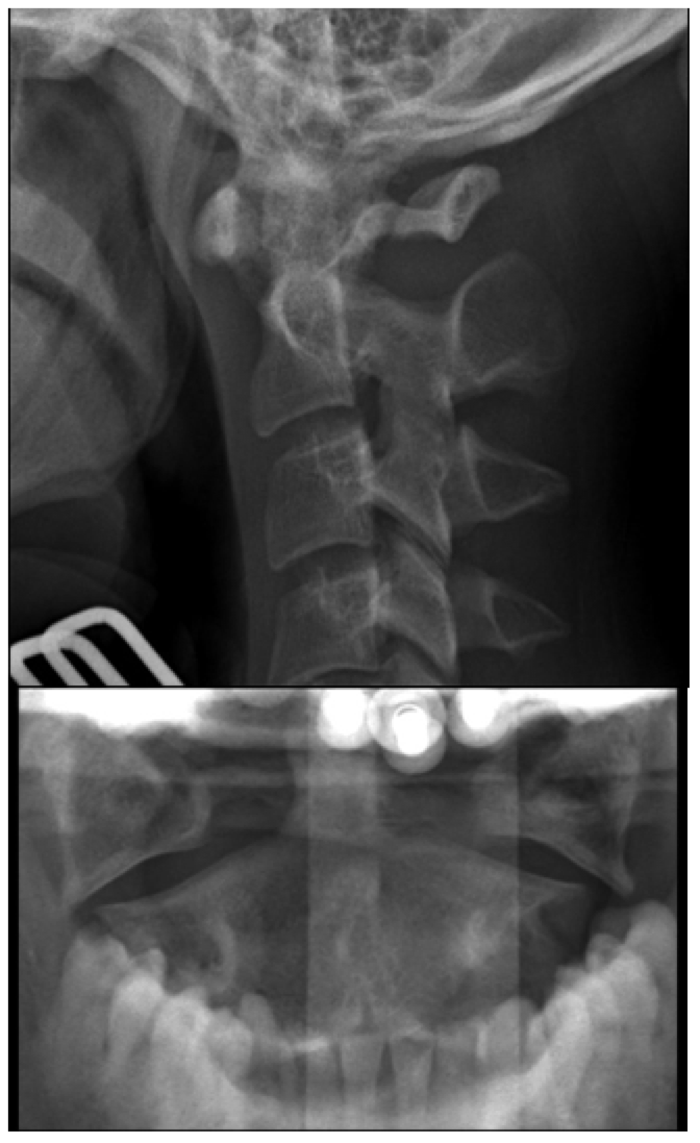

C-spine Radiographs

• Why are children more prone to high cervical spine injuries?

• Name 7 normal variants of pediatric cervical spine

A

• By 8 to 9 years of age, cervical spine reaches adult proportions

• Cervical spine injuries in children usually occur high - from the occiput to C3 vertebra

• Fulcrum of motion in children is at the C2-C3 level rather than at the C5-C6 level in adults

• Owing to hypermobility of the c-spine because of ligamentous laxity, shallow and angled facet joints, anteriorly wedged vertebrae, and underdeveloped spinous processes

• Weak neck muscles, underdeveloped odontoid process, and large head also contribute to instability of the c-spine

• For screening, obtain lateral, AP, and odontoid views of the cervical spine

• Need for odontoid view sometimes questioned

• Some experts believe lateral view in children under 5 years sufficient

• False negative rate of single lateral view 21 to 26%

Approach

• Every lateral c-spine view should visualize at least the top of T1, of not, may need swimmer’s

• Lateral

• Upper C-spine

• Atlantodens interval (< 5 mm)

• Spinolaminar line should intersect with opisthion

• Relationship between basion and odontoid and posterior vertebral line for atlantooccipital dislocation - should be less than 12 mm (?), head usually dislocated anterior on cervical spine

• Look at odontoid

• C2 on C3 subluxation, C2 pedicles

• Lower C-spine

• Anterior vertebral body line

• Posterior vertebral body line

• Articular pillars

• Spinolaminar line

• Disc spaces should be roughly equal

• Interspinous spaces should be uniform

• Kyphotic deformity

• Prevertebral tissues (see below)

• Odontoid

• Lateral bodies with respect to axis

• Atlantodental spaces should be symmetric

• AP

• Spinous processes - will be malaligned in facet joint dislocation

• Uncinate processes

• Pedicles

Normal Pediatric Variants:

• ADI = atlantodens interval or distance between anterior wall of the dens (odontoid process) and posterior wall of the atlas’ anterior ring

• In children less than 5 mm is normal

• If greater than 5 mm, suspect ligamentous disruption

• Pseudo spread of the atlas on the axis can be seen on the odontoid view

• Pseudo Jefferson fracture

• Up to 6 mm of displacement of lateral masses relative to the dens can be seen commonly in patients under 4 years and may be seen up to 7 years of age

• Pseudo subluxation of C2 on C3

• C2 on C3 and to a lesser extent C3 on C4 can have physiologic displacement

• Check posterior cervical line (line between anterior aspects of spinous processes of C1, 2, and 3) - should line up within 1 mm

• If the posterior cervical line does not overlap anterior aspect of spinous process of C2 by more than 2 mm, true injury is present

• Abnormal posterior cervical line suspect occult hangman fracture of C2

• Absence of lordosis may be seen up to 16 years

• Posterior intraspinous distance should not be more than 1.5 the distance of the levels above and below the level in question

• In children, flexion can cause fanning of the C1 and C2 spinous processes (tight ligamentous connection of C1 to skull base)

• Anterior wedging of up to 3 mm of the vertebral bodies

• Can be marked at C3

• Normal physeal plates - expected location, smooth and regular, subchondral sclerotic lines

• vs fracture - occur at any location, irregular lines, no sclerosis

• Prevertebral space of less than 6 mm in children is normal

• Widening of prevertebral space can be due to expiration - if widened, repeat in slight extention and inspiration